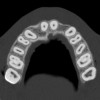

Based upon the intraoral examination and periapical radiographs, additional orthodontic intervention was r.commended to move and rotate the roots to gain enough space for implant placement. This information was conveyed to both the parents and to the treating orthodontist. After several additional months, a panoramic radiograph was provided by the orthodontist to evaluate the distance between the clinical crowns and tooth roots (Figure 3). The lack of sharpness, definition, and radiographic artifacts made it impossible to determine whether implants could be successfully placed based on the 2D panoramic image. This diagnostic predicament was discussed with the patient and his parents, and it was suggested that a CT scan would be necessary to accurately assess the bone topography and spatial orientation of the adjacent roots. The parents agreed, and the patient was given a prescription for a CT scan study at a local radiology center.

Figure 3  After orthodontic therapy, the radiograph did not provide enough diagnostic information to determine if implants could be placed.

Figure 3